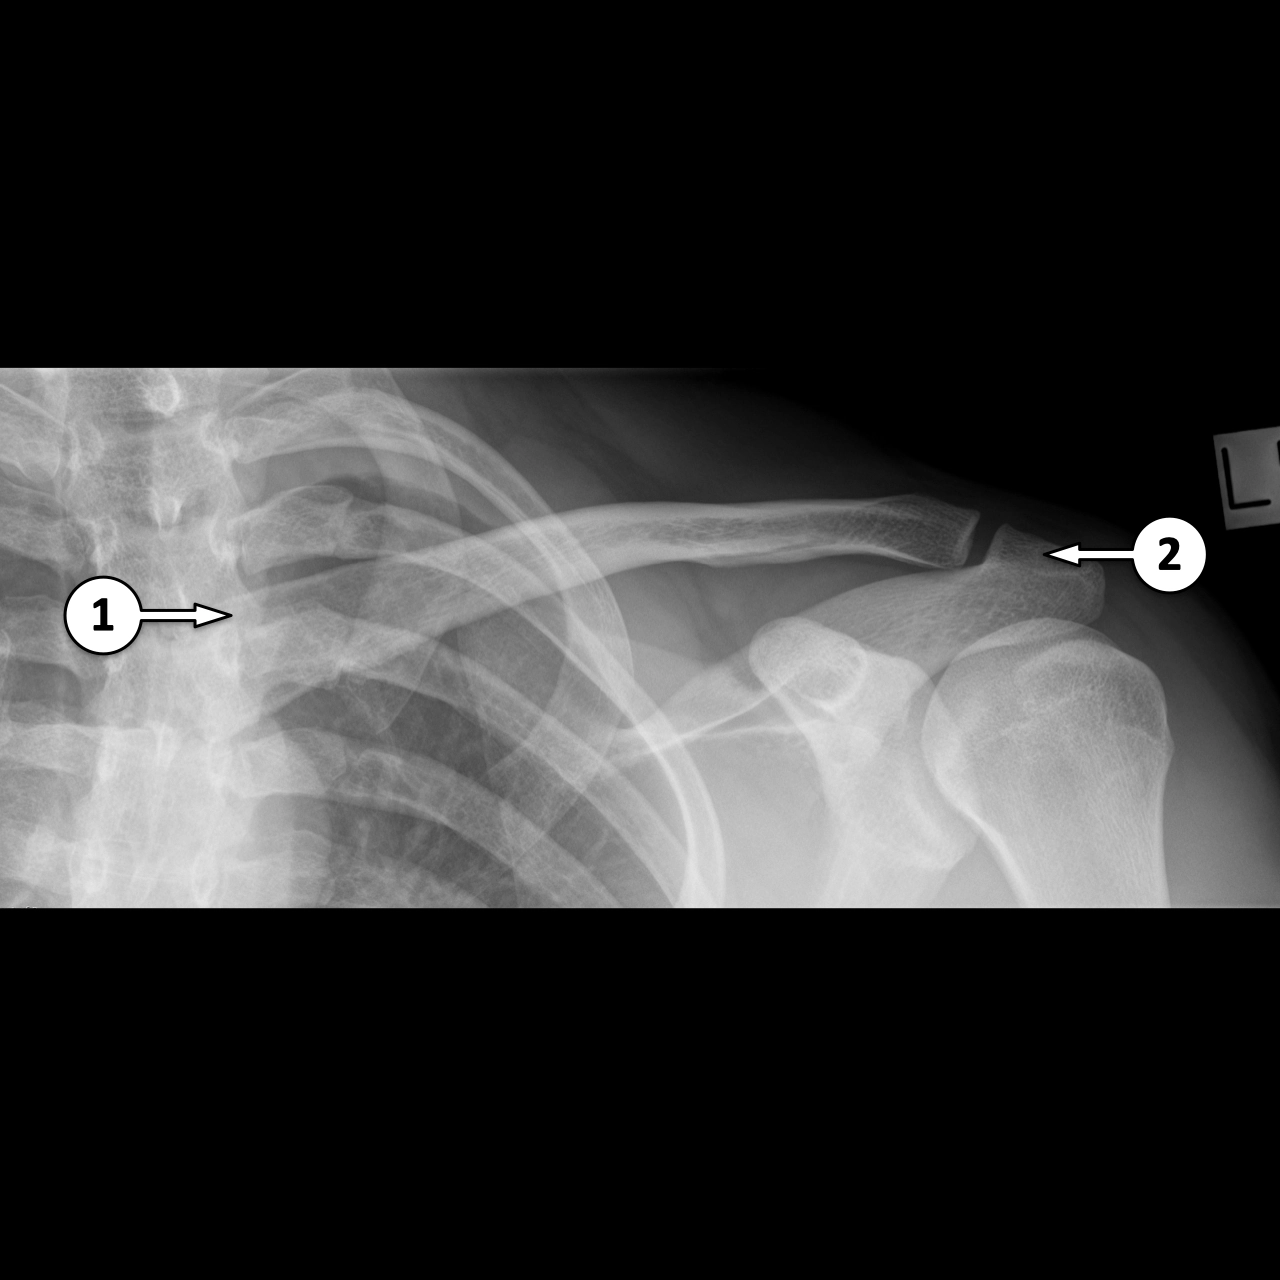

X Quang xương đòn